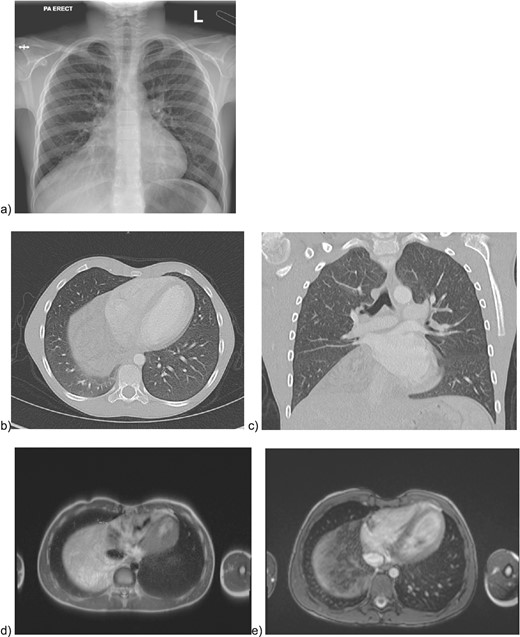

During a renal ultrasound to evaluate dysuria in a 10 year old male, an incidental mass was identified obscuring the right hemidiaphragm leading to further workup. He had no respiratory symptoms, though had reduced air entry on auscultation at the right base. Chest X ray (Fig. 1a) confirmed silhouetting of the right heart border. CT with intravenous contrast (Fig. 1b and c) showed a lower anterior mediastinal mass measuring 10 cm × 9 cm × 8 cm. It was heterogeneous and contained areas of fatty and soft tissue attenuation concerning for a teratoma or thymolipoma. Cardiac-gated chest MRI was then obtained which showed that the mass likely originated in the thymus and extended adjacent to the right atrial appendage and right atrium onto the diaphragm but did not invade pericardium or diaphragm (Fig. 1d and e). The signal was most consistent with a fatty tumor consistent with a giant thymolipoma.

Preoperative imaging of the mediastinal mass. a) CXR illustrating the obscured right hemidiaphragm that was incidentally detected leading to further workup; b) axial and c) coronal CT images with intravenous contrast; e) MRI imaging with axial T2 HASTE sequence f) MRI axial VIBE sequence.